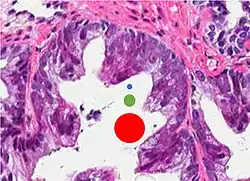

-

Intraductal carcinoma of the prostate with an infiltrative growth pattern may be morphologically difficult to distinguish from invasive cancer. One focus shows comedonecrosis (arrow), morphologically suggesting Gleason pattern 5 invasive carcinoma (a haematoxylin and eosin, b CK5/6)[20] -

Intraductal carcinoma of the prostate with very patchy basal cells identified by immunohistochemistry. At least some of the glands lacking basal cell immunoreactivity represent intraductal rather than invasive carcinoma (a haematoxylin and eosin, b CK 5/6)[20]